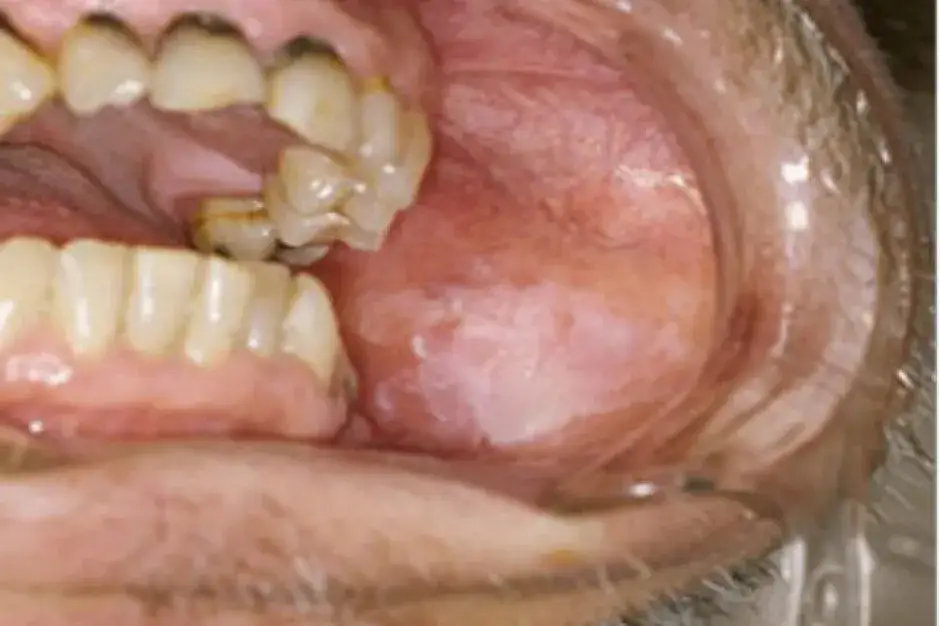

Czerwone i białe plamy, których nie wolno ignorować

Jednym z pierwszych sygnałów ostrzegawczych mogą być zmiany w kolorze błony śluzowej jamy ustnej. Szczególną uwagę powinniśmy zwrócić na trwałe plamy, które nie znikają samoistnie i nie dają się zetrzeć.

Leukoplakia to biała, twarda plama na błonie śluzowej, która nie ustępuje po próbie starcia. Choć sama w sobie nie jest rakiem, jest uważana za zmianę przednowotworową i wymaga ścisłej obserwacji lekarskiej, ponieważ może przekształcić się w nowotwór złośliwy. Jej pojawienie się jest często związane z przewlekłym drażnieniem błony śluzowej, na przykład przez palenie tytoniu.

Erytroplakia manifestuje się jako czerwona, aksamitna plama, często o nierównych, postrzępionych brzegach. Jest to zmiana o znacznie wyższym potencjale złośliwości niż leukoplakia i wymaga natychmiastowej konsultacji lekarskiej. Jej jaskrawoczerwony kolor wynika z obecności nieprawidłowych naczyń krwionośnych w obrębie błony śluzowej.

Owrzodzenia w jamie ustnej to częsty problem, jednak każde, które utrzymuje się dłużej niż kilka tygodni, powinno wzbudzić naszą czujność. Zmiany nowotworowe często przybierają formę owrzodzeń, które mogą być mylone ze zwykłymi aftami.

Typowe owrzodzenie nowotworowe często charakteryzuje się tym, że jest niebolesne lub tylko lekko bolesne. Może mieć nieregularny kształt, a jego brzegi są zazwyczaj twarde i lekko uniesione w stosunku do otaczającej tkanki. W przeciwieństwie do zwykłej ranki, nie wykazuje tendencji do szybkiego gojenia.